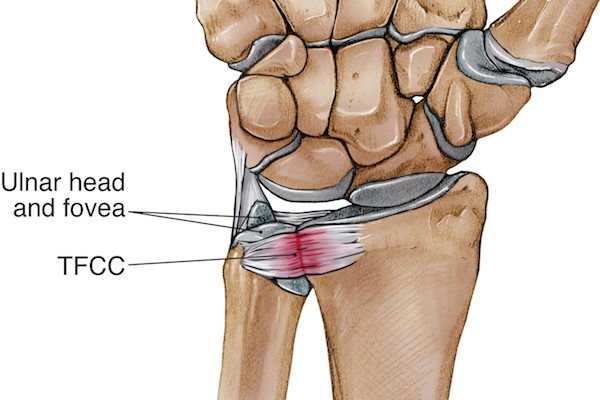

수부에서 가장 흔하게 볼 수 있는 손상중에 하나가 바로 삼각섬유연골 복합체의 손상입니다. 정형외과에서는 TFCC 손상이라고 흔히들 약어로 부르게 됩니다. 이는 요수근 관절에서 원위 요척관절은 회내, 회외 운전의 축(Pivot) 역할을 하는 곳입니다.

삼각 섬유연골 복합체는

원위 요척인대

관절판(articular disc)

동종 반월연골판(menisal allograft)

척수근골인대(ulnocarpal ligament)

척측 관절낭(ulnar capsule)

척수근 신근의 건초하부

로 구성되어 있습니다.

이들의 기능은 척골두를 덮어 원위 요골의 관절면이 연장되게 하며, 척수근 관절에 부하되는 힘의 일부를 흡수하고, 전완부의 회전시 척골과 요골을 결합시키며, 척골과 요골을 연결시켜 척측의 수근골을 지지합니다. 척골 경상돌기 골절이 동반될 수 있으며, 원위 요척관절, 척수근관절과 기능적, 구조적으로 연결되어 있으므로 주의깊게 관찰하여야 합니다.